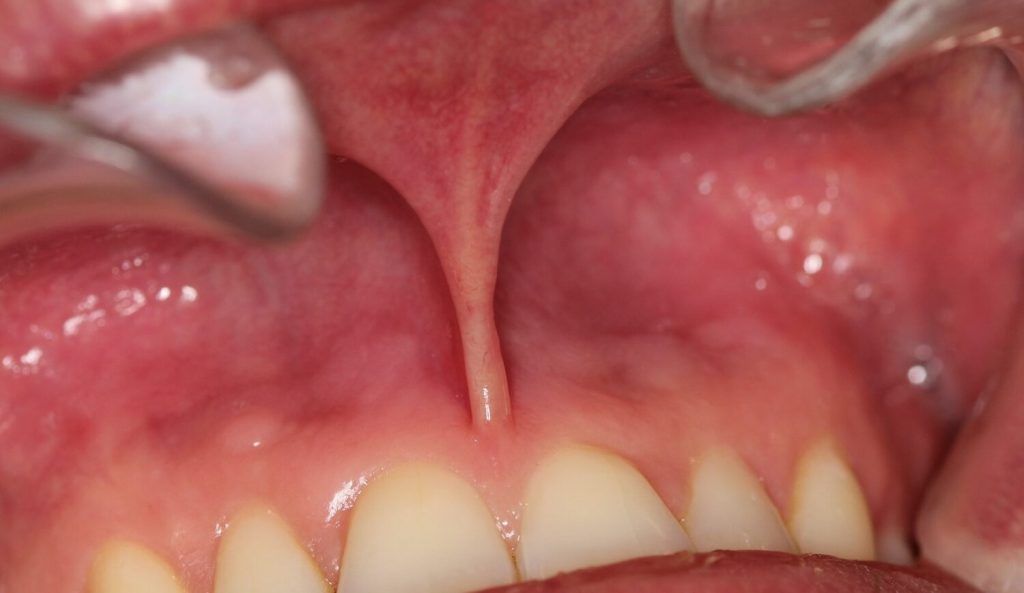

A new study has been initiated at the University of Gothenburg to study the effects on oral health from using nicotine pouches. The university has released a statement detailing that the study is being initiated because a number of dental patients referrals from dental clinics to the University. These patients have gum damage that differs from what is commonly seen in users of traditional tobacco-based snus. This statement has been widely reported by Swedish news media.

A pilot study with 23 Swedish dentists who were daily pouch users of either tobacco snus or nicotine pouches (referred to as “white snus” in the University of Gothenburg statement , several of which had similar gum issues to those documented by Dr Gale including irritated or inflamed gums, snus lesions and receding gums. In our test the occurrence and severity of gum irritation and snus lesions was reduced significantly when users switched to using only Stingfree pouches for 5 weeks. Stingfree pouches have the same type of contents as ordinary pouches but the pouch itself has a protective layer called PROTEX that prevents direct contact between the pouch contents and the users’ gums.